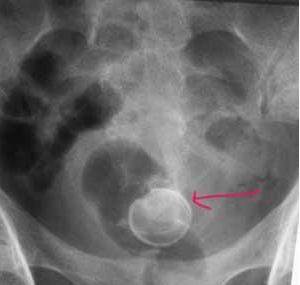

2、X线检查:膀胱区平片能看到膀胱结石患者体内不透光的结石阴影。